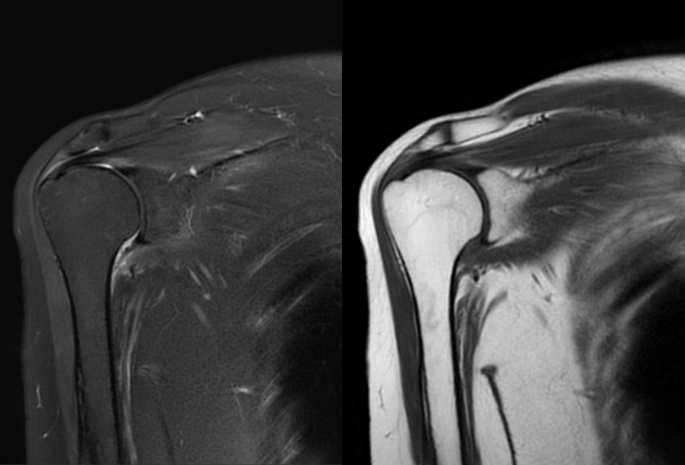

軽量であると共に、コイルサイズが長さ79cm幅66cmと、かなりの大判サイズのため有効感度面積が広く、柔軟性が高いので汎用性に富み、全身DWI含めた躯幹部の撮影から(図4、5)、肩関節などの四肢まであらゆる部位に使用が可能となっています。そのため部位によって使用するコイルの選択に迷う事がなくなり、患者へのコイル装着を容易に行うことができるようになりました。特に肩などの磁場不均一部位での検査でもAIR AAコイルの感度均一性が高いので、患者体位設定の不備による感度ムラが起きにくく、常にSNRの高い画像を提供可能となりました(図6)。

図6 AIR AAコイルで撮像した肩関節画像(撮像セッティングは図3を参照)